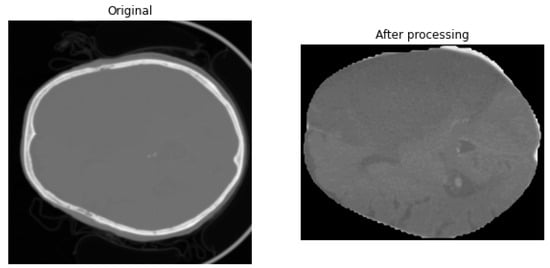

Figure 2 presents an example from the dataset after preprocessing, illustrating the results of image processing aimed at improving data quality and enhancing key features for further analysis.

Figure 2. CT images before and after preprocessing: on the left: original and on the right: after preprocessing.